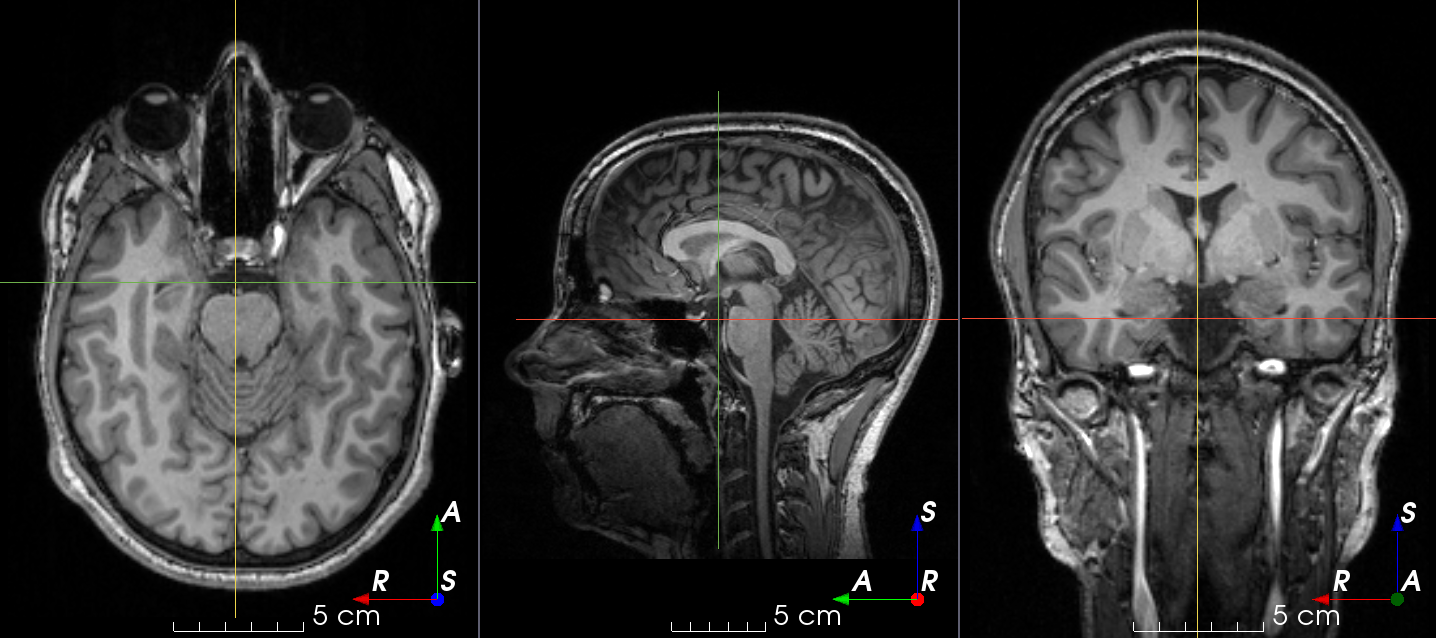

Add random MRI spike artifacts.

Also known as Herringbone artifact , crisscross artifact or corduroy artifact, it creates stripes in different directions in image space due to spikes in k-space.